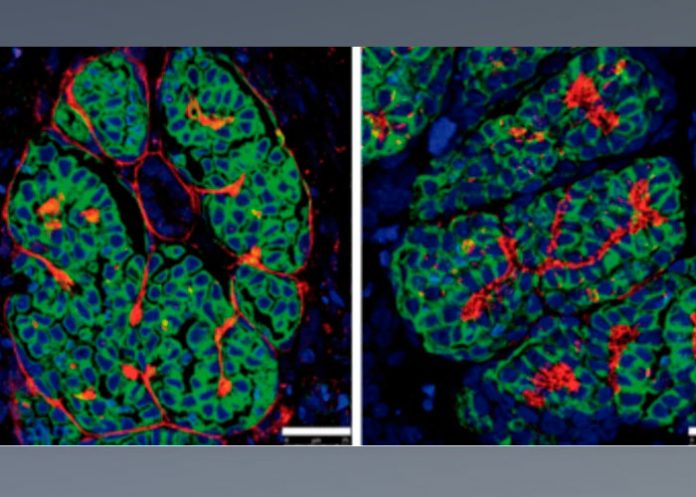

«Este organoide, además, lo hemos conseguido cultivar en un biomaterial, un hidrogel, que simula la dureza del ambiente embrionario, la placenta o el huevo, y, con la membrana de un embrión de pollo hemos logrado que se vascularice, que tenga riego sanguíneo e incluso que crezca«, detalló Montserrat.

«Hemos visto que en nuestro biomaterial -un hidrogel- con las membranas embrionarias de huevos, los mini riñones se vascularicen en dos o tres días imitando artificialmente el microambiente en el que se desarrollan los riñones en la naturaleza».

Montserrat, que reconoce que para los neófitos la suya parece una investigación «muy Frankenstein», destacó que el riñón «es un órgano muy complejo, está implicado en muchas enfermedades primarias y afectado por otras secundarias» y con este nuevo avance pueden ver «cómo se forman los vasos sanguíneos en el riñón, cómo irrigan, cómo actúan y crecen las nefronas».